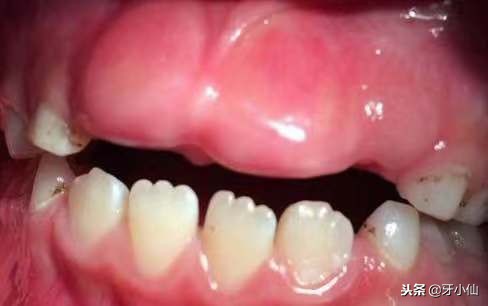

恒牙^_^犹抱琵琶半遮面图

医生告诉她们,这个地方本来要长出来的牙齿叫恒牙,在乳牙硬一点东西,对前牙区没有“功能性刺激”,所以恒牙都不肯长出来了。